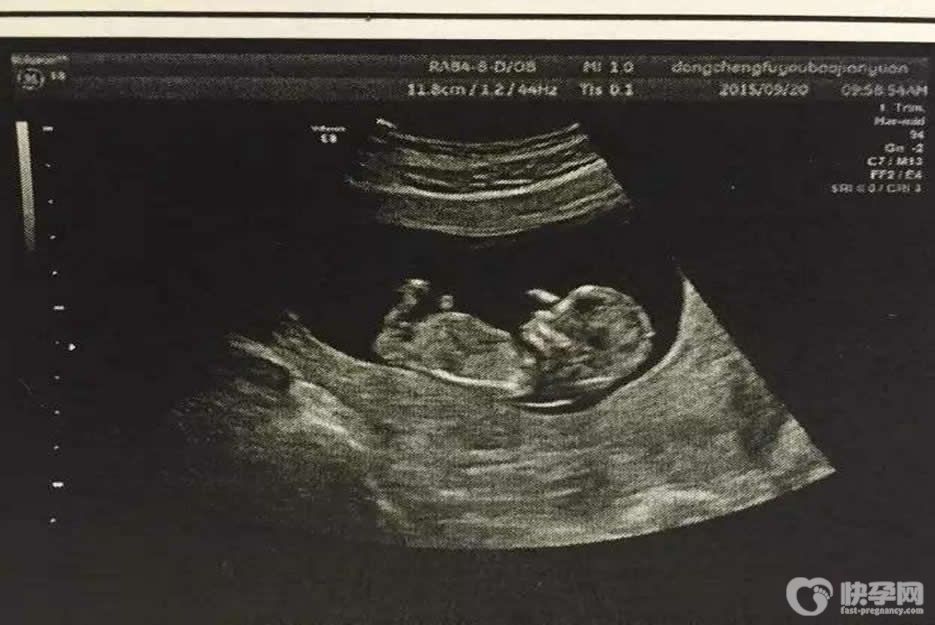

b超对胎儿有影响吗-明白这两点让你远离b超误区

b超对胎儿有影响吗?怀孕期间,孕妈妈们要做许许多多的检查,而b超就是其中之一。孕妈妈在怀孕期间,医生会安排三次B超检查,分别为孕早期、孕中期、孕晚期,根据胎儿发育..